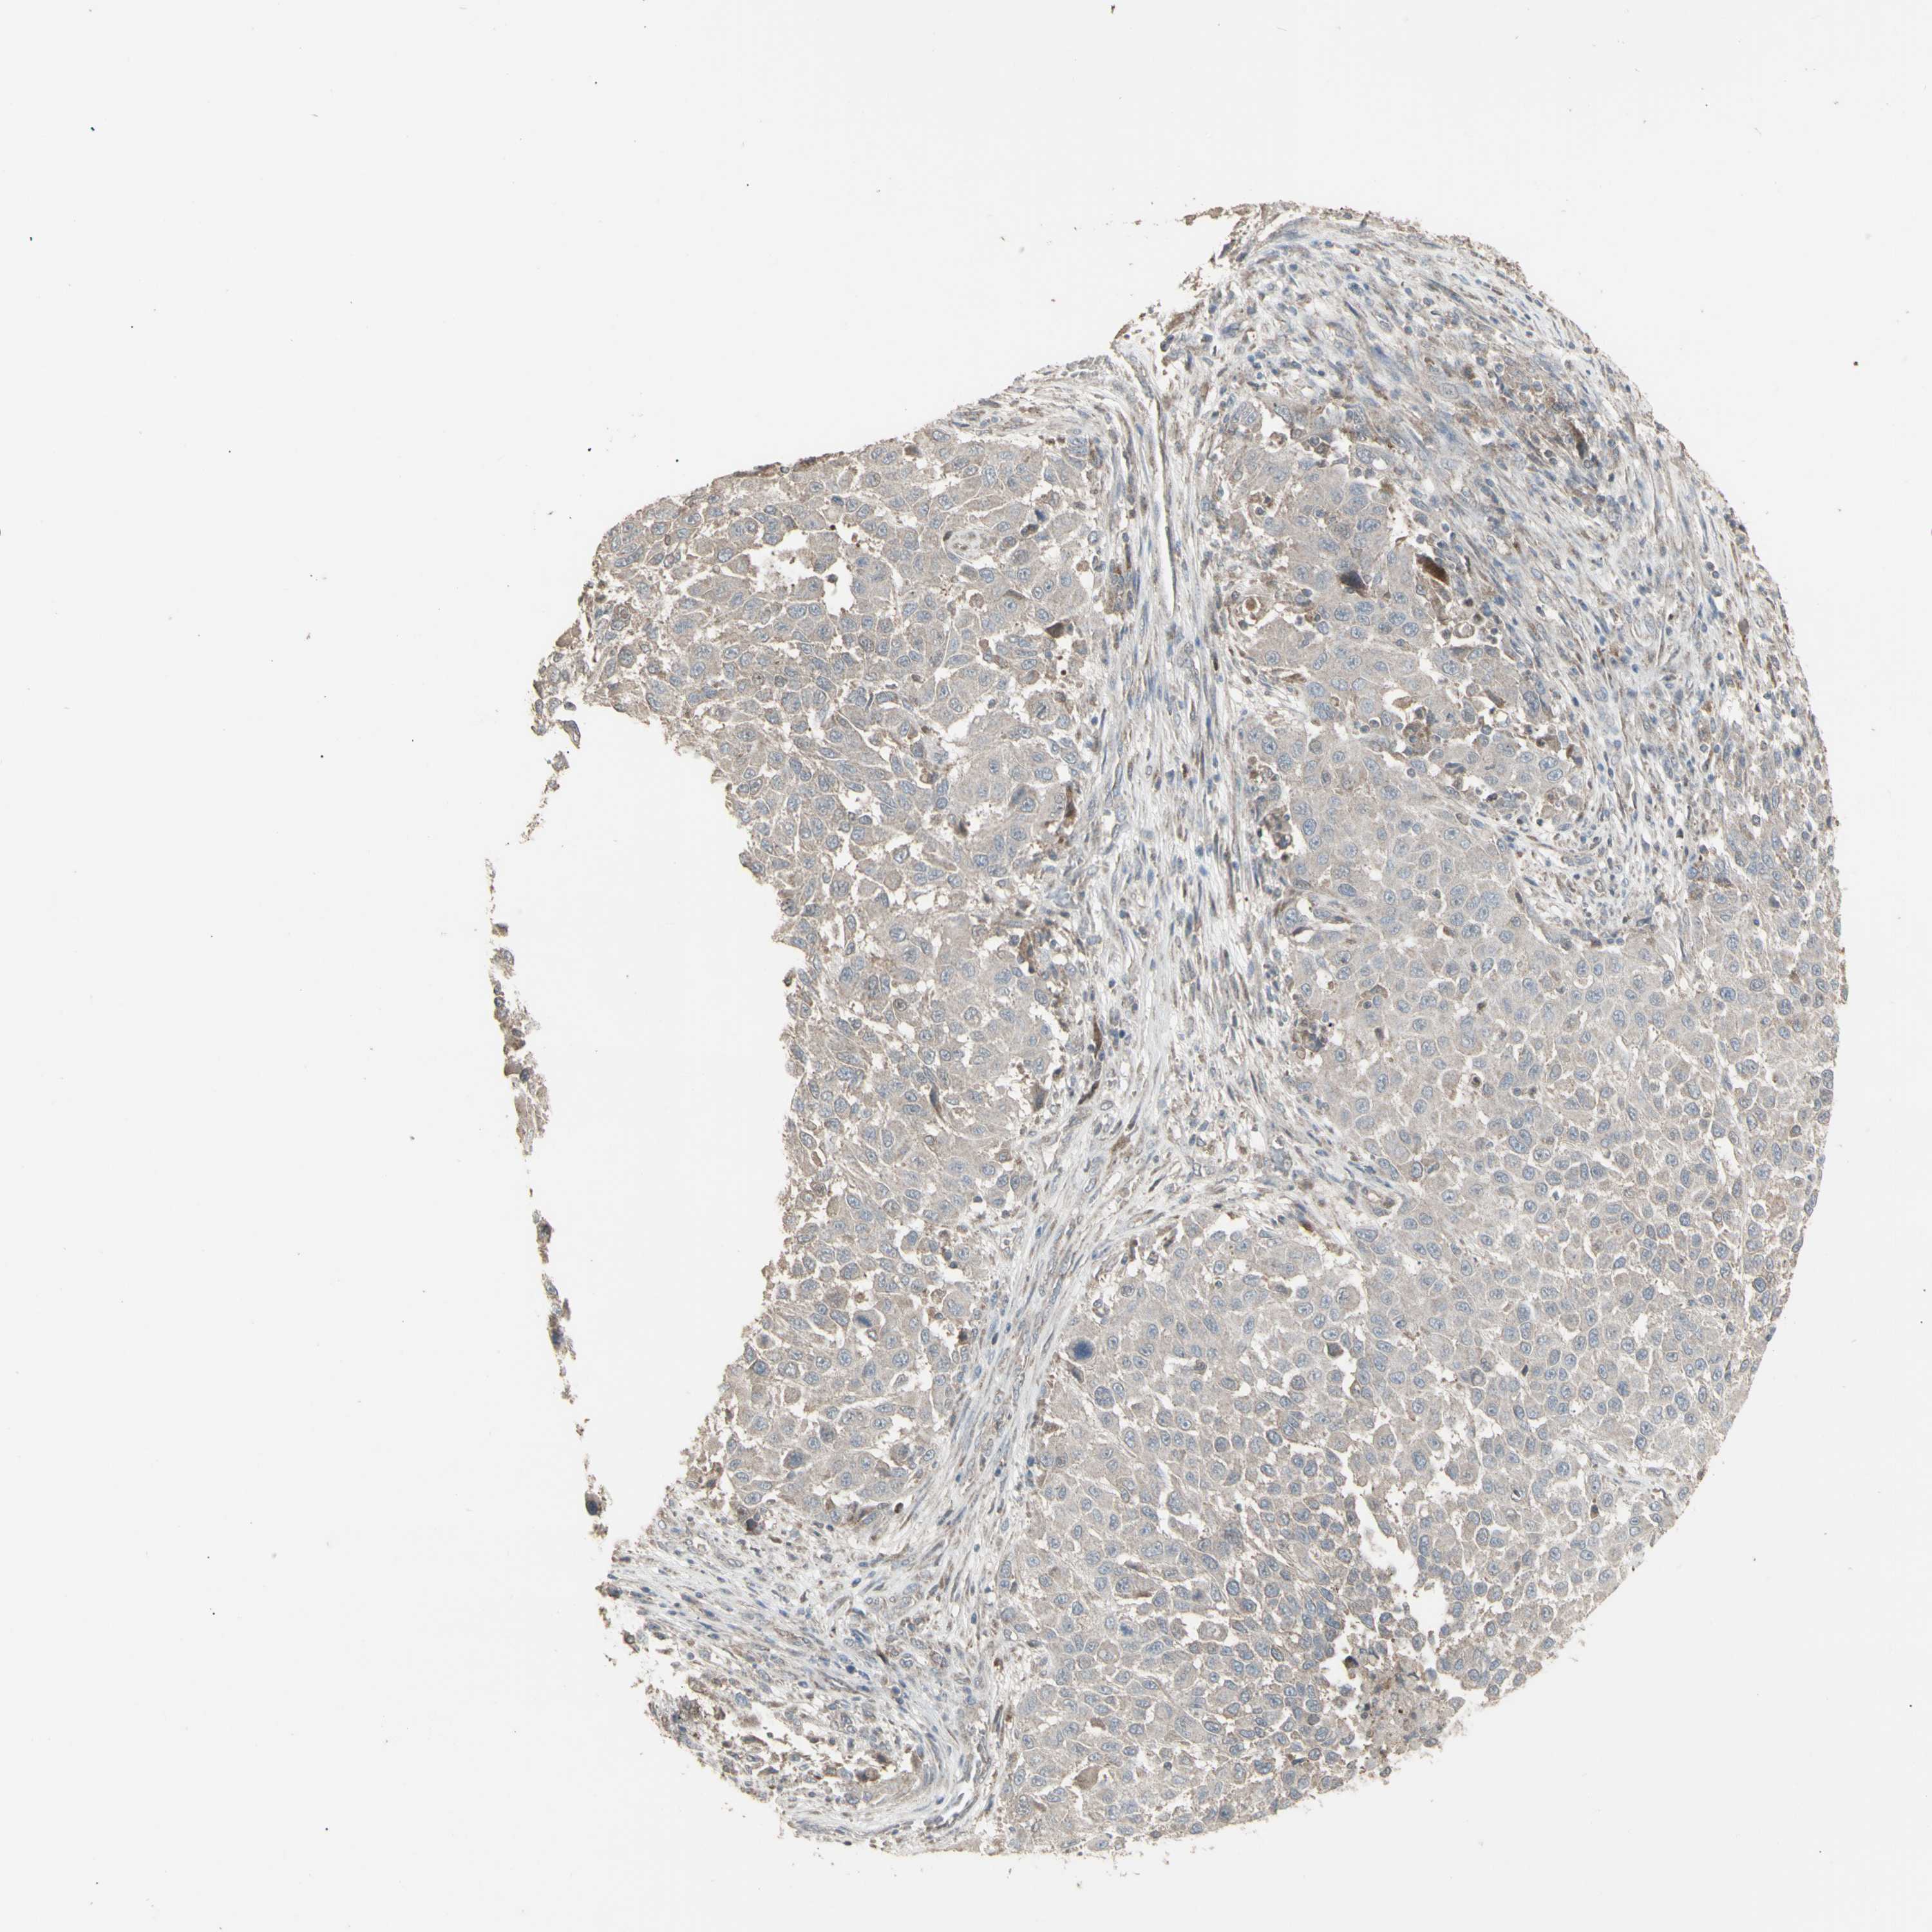

MELANOMA - Protein expressioni

A mouse-over function shows sample information and annotation data. Click on an image to view it in a full screen mode. Samples can be filtered based on level of antibody staining by selecting one or several of the following categories: high, medium, low and not detected. The assay and annotation is described here.

Note that samples used for immunohistochemistry by the Human Protein Atlas do not correspond to samples in the TCGA dataset.

Antibody stainingi

Antibody staining in the annotated cell types in the current human tissue is reported as not detected, low, medium, or high, based on conventional immunohistochemistry profiling in selected tissues. This score is based on the combination of the staining intensity and fraction of stained cells.

Each image is clickable and will lead to virtual microscopy that enables deeper exploration of all samples and also displays staining intensity scores, fraction scores and subcellular localization as well as patient and tissue information for each sample.

Antibody HPA002633

Antibody HPA046758

Antibody CAB010906

Staining

High

Medium

Low

Not detected

Intensity

Strong

Moderate

Weak

Negative

Quantity

>75%

75%-25%

<25%

None

Location

Nuclear

Cytoplasmic/membranous

Cytoplasmic/membranous,nuclear

Malignant melanoma, NOS

Malignant melanoma, Metastatic site

Malignant melanoma in situ